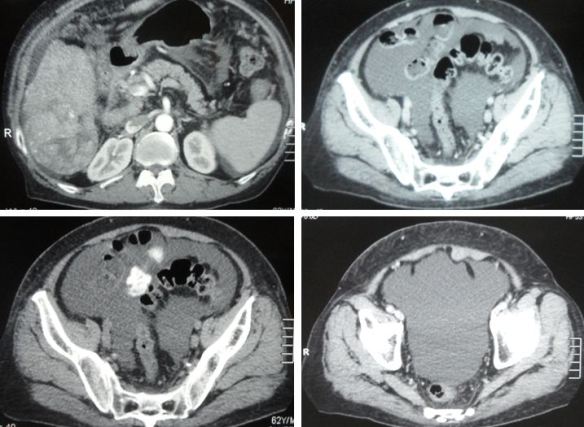

ST is a 62-year-old man from Perak. Two years ago (May 2018) he was diagnosed with cancer of the appendix and adjacent caecum.

In March 2020, ST started to have abdominal pain and at times, he vomited. He went back to the same hospital where he had his surgery. A CT scan was done and revealed:

• Acute small bowel obstruction with no evidence of tumour recurrence.

• Liver lesions – cyst or metastasis ?

• Bilateral small renal cyst.

On 25 April 2020, ST went back to the hospital again due to small bowel obstruction. He underwent a laparotomy on 29 April 2020.

Intraop finding: Jejunoileal junction tumour infiltrated by posterior abdominal wall.

Histopathology of small bowel, retroperitoneal nodule and omentum: Adenocarcinoma with lymphovascular invasion.

On 8 May 2020 ST suffered bile leak from the wound site. He had to undergo another operation – relaparotomy, jejunostomy done stoma created. This means ST had to wear a bag.

A CT scan done on 4 August 2020 showed:

• Progression of disease evidenced by increased number and size of cystic liver lesions – likely metastasis.

• No evidence of recurrence.

• Prostatomegaly.